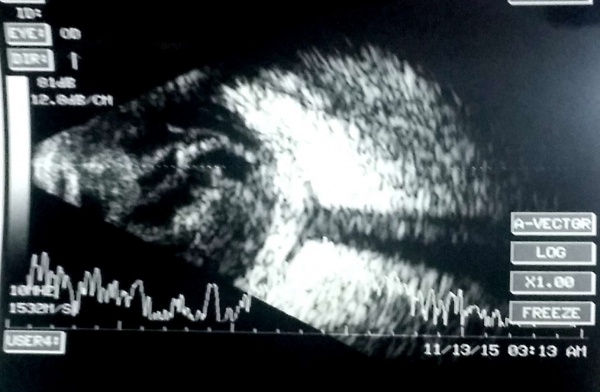

A case of choroidal hemangioma[6] with exudative RD. Note the limited after-movements.